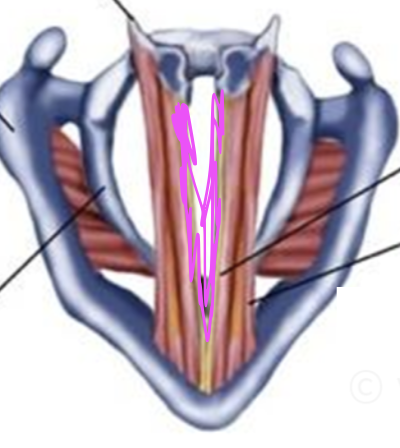

What is this muscle in purple?

Thyromuscularis (VF relaxer, pitch down)